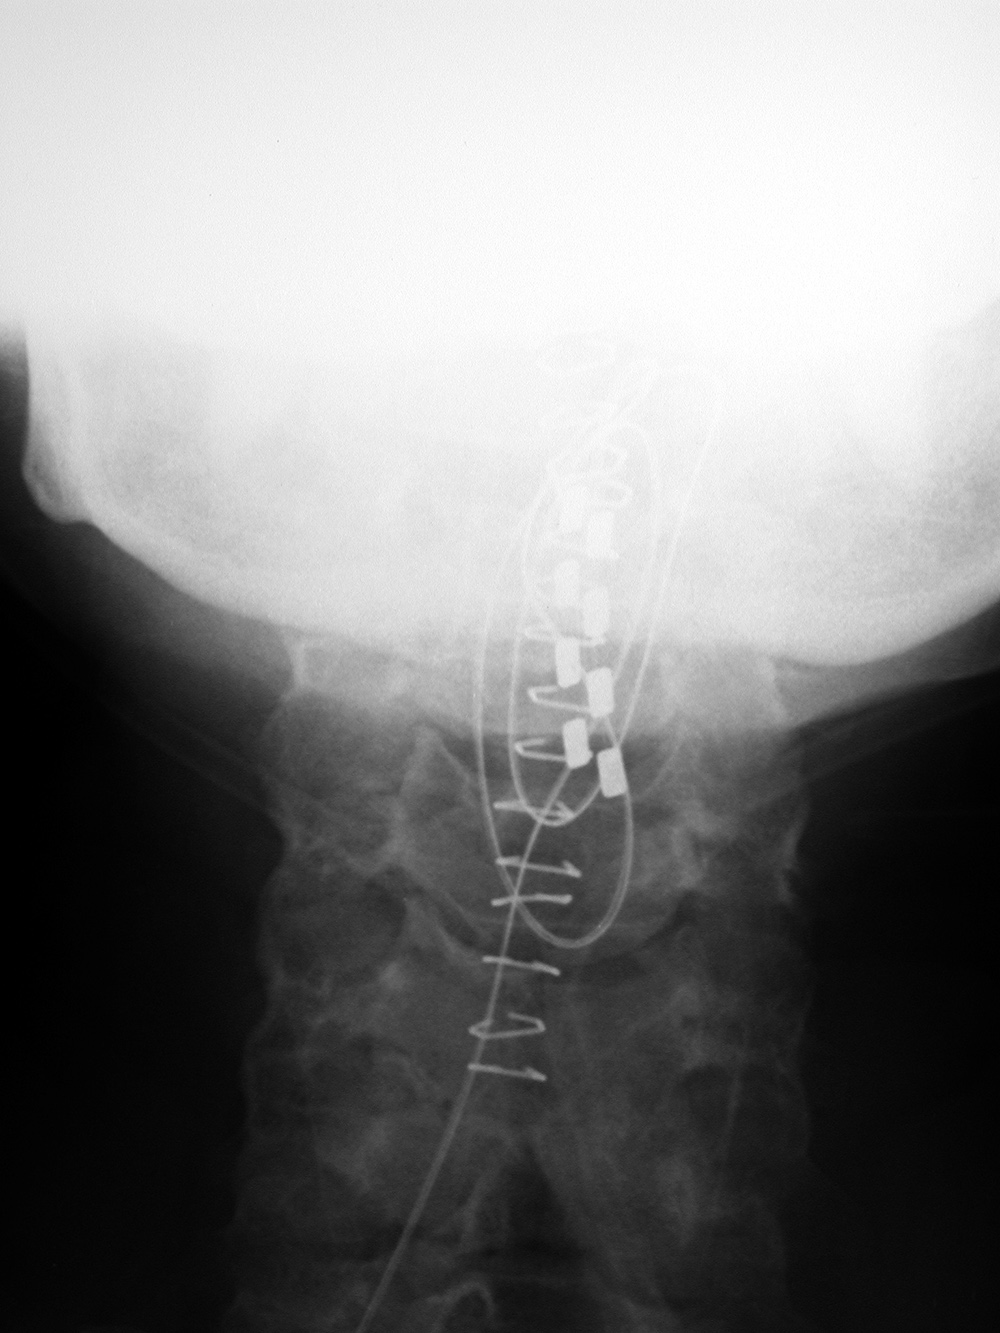

| Child with severe intracranial and cervical spine injuries with bilateral cranial stabilization tongs, an endotracheal tube, an oroogastric tube, and a feeding tube entering via the nose.

From Hunter, 2004 |

Cranial (head) tongs |

Cranial (head) tongs are used to stabilize the head and neck in a patient with a cervical spine fracture. One or more screws penetrate the outer table of the skull on each side. They are connected to each other by horizontal or vertical bars on each side that are attached to an external traction device.